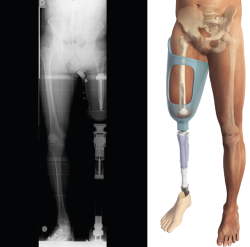

Siempre que la viabilidad de una amputación TT no sea posible, debemos considerar la DR antes que la amputación TF, donde la preservación de los cóndilos femorales facilita la adaptación de un encaje con apoyo distal del muñón (Figura 1). Clínicamente, el apoyo distal es la ventaja más importante en las DR con respecto a la amputación TF, ya que permite transferir directamente la carga distal al muñón femoral y, de este modo, aumentar la independencia en la marcha y reducir el consumo de oxígeno(6,7).

Figura 1. Desarticulación de rodilla.